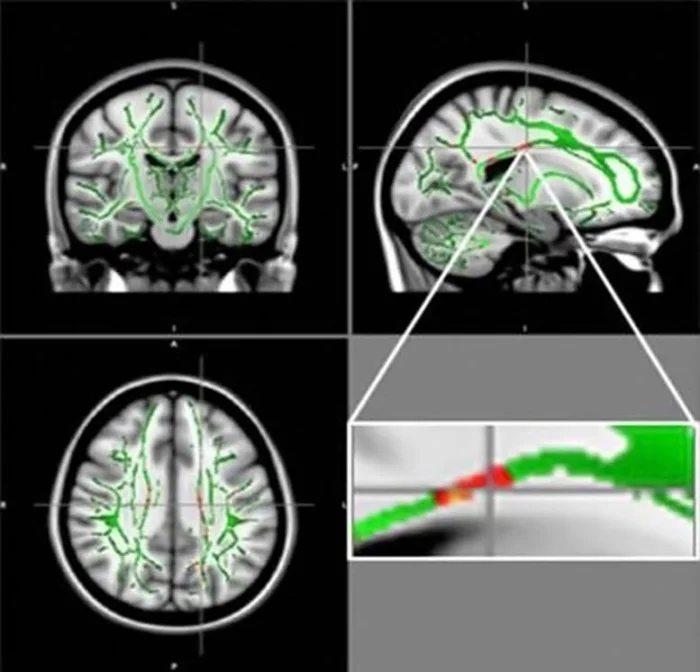

Чтобы точно изучить мозг, исследователи использовали метод диффузионно-взвешенной магнитно-резонансной томографии (DW-MRI), в котором диффузия молекул воды используется для создания контраста в МРТ.

В этом конкретном случае они использовали специальный тип DW-MRI, называемый диффузно-тензорной визуализацией, для картирования трактографии белого вещества в мозге 120 подростков. 61 из них были здоровыми подростками, а 59 страдали ожирением. Все участники были в возрасте от 12 до 16 лет.

Исследователи сравнили результаты сканирования МРТ и извлекли скалярное значение (для каждого мозга), называемое фракционной анизотропией (ФА). Значение указывает на состояние белого вещества в мозге: чем ниже ФА, тем выше повреждение белого вещества.

Они обнаружили снижение значений ФА у всех пациентов с ожирением. Уменьшение ФА наблюдалось в двух разных частях их мозга:

- Мозолистое тело: толстая полоса нервных волокон, которая расщепляет доли коры головного мозга на правое и левое полушария.

- Орбитофронтальная извилина: префронтальная область коры в лобных долях, которая участвует в процессе принятия решений.